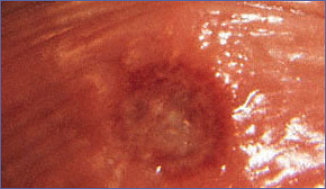

Human papilloma virus (HPV) adı verilen virüsün cinsel temasla genital bölgeye yerleşmesi sonucu oluşan değişik sayı ve büyüklükte kitlelerdir. Kadında erkeğe göre daha sık belirti verir. Kitleler çok ufak olabileceği gibi, çok sayıda kitlenin birleşmesiyle adeta karnabahar şeklini olabilirler. HPV çok bulaşıcı bir virüstür ve cinsel birleşme olmaksızın yalnızca genital bölgelerin yakın teması ve ortak tuvaletlerden bile bulaşabilir. Verrüsü olan kişilerle cinsel ilişkiye giren kişilerin yaklaşık %60 ına da siğilin bulaştığı düşünülmektedir. Siğiller genellikle temastan yaklaşık üç ay sonra ortaya çıkar ancak yıllarca hiç ortaya çıkmayan siğiller de olabilir. İngiltere’de yapılan çalışmada 16 yaşından küçük genç kadınların % 10 unda bir veya daha fazla HPV virüsüne rastlanmıştır.

Kanser: HPV virüsün bazı tiplerinin kanserojen (kanser yapıcı) özelllikler taşımaktadır. Kanserojen özelliği olan alt tipler bazen kondilom yapmadan sessiz bir şekilde vücuda girerler. Bu virüsleri taşıyan erkeklerde penis kanseri riski, kadınlarda da serviks (rahim ağzı) kanseri riski artmıştır. Gebelik Sorunları: Gebe kadınlarda idrar yollarına ait sorunlar olabilir. Bazen doğum yolu darlığına neden olabilir. Nadiren de olsa çocuğun solunum yollarını tıkayacağı için operasyon gerektiren "laringeal papilomatosis"e neden olabilir. Gebelik hormonlarına bağlı genital siğillerin sayısı artabilir büyüyebilir veya kanayabilir.